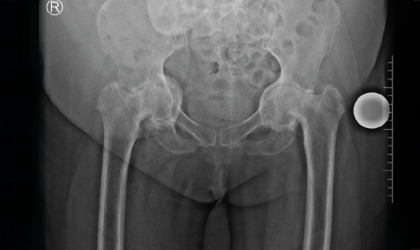

This 68 year old lady has a condition called protrusio where the socket becomes weak and protrudes into the pelvis. She was on a wheel chair for over a year with two caretakers to care for her. She needed very complex hip replacements which required a lot of planning. We had to bone graft the socket as well. The hip replacements have made her independent and painfree. Now she walks without support.

Due to the severe protrusio deformity, detailed planning was crucial. A custom approach involving bone grafting and complex hip replacement components was outlined to rebuild the damaged socket and restore alignment.